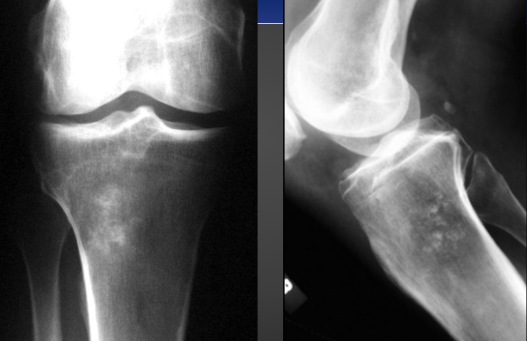

Osteosarcoma on X-ray (knee)

Osteosarcoma Mixed on X-ray